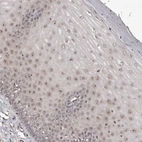

Immunohistochemical staining of human cervix, uterine shows distinct nucleolar positivity in squamous epithelial cells.